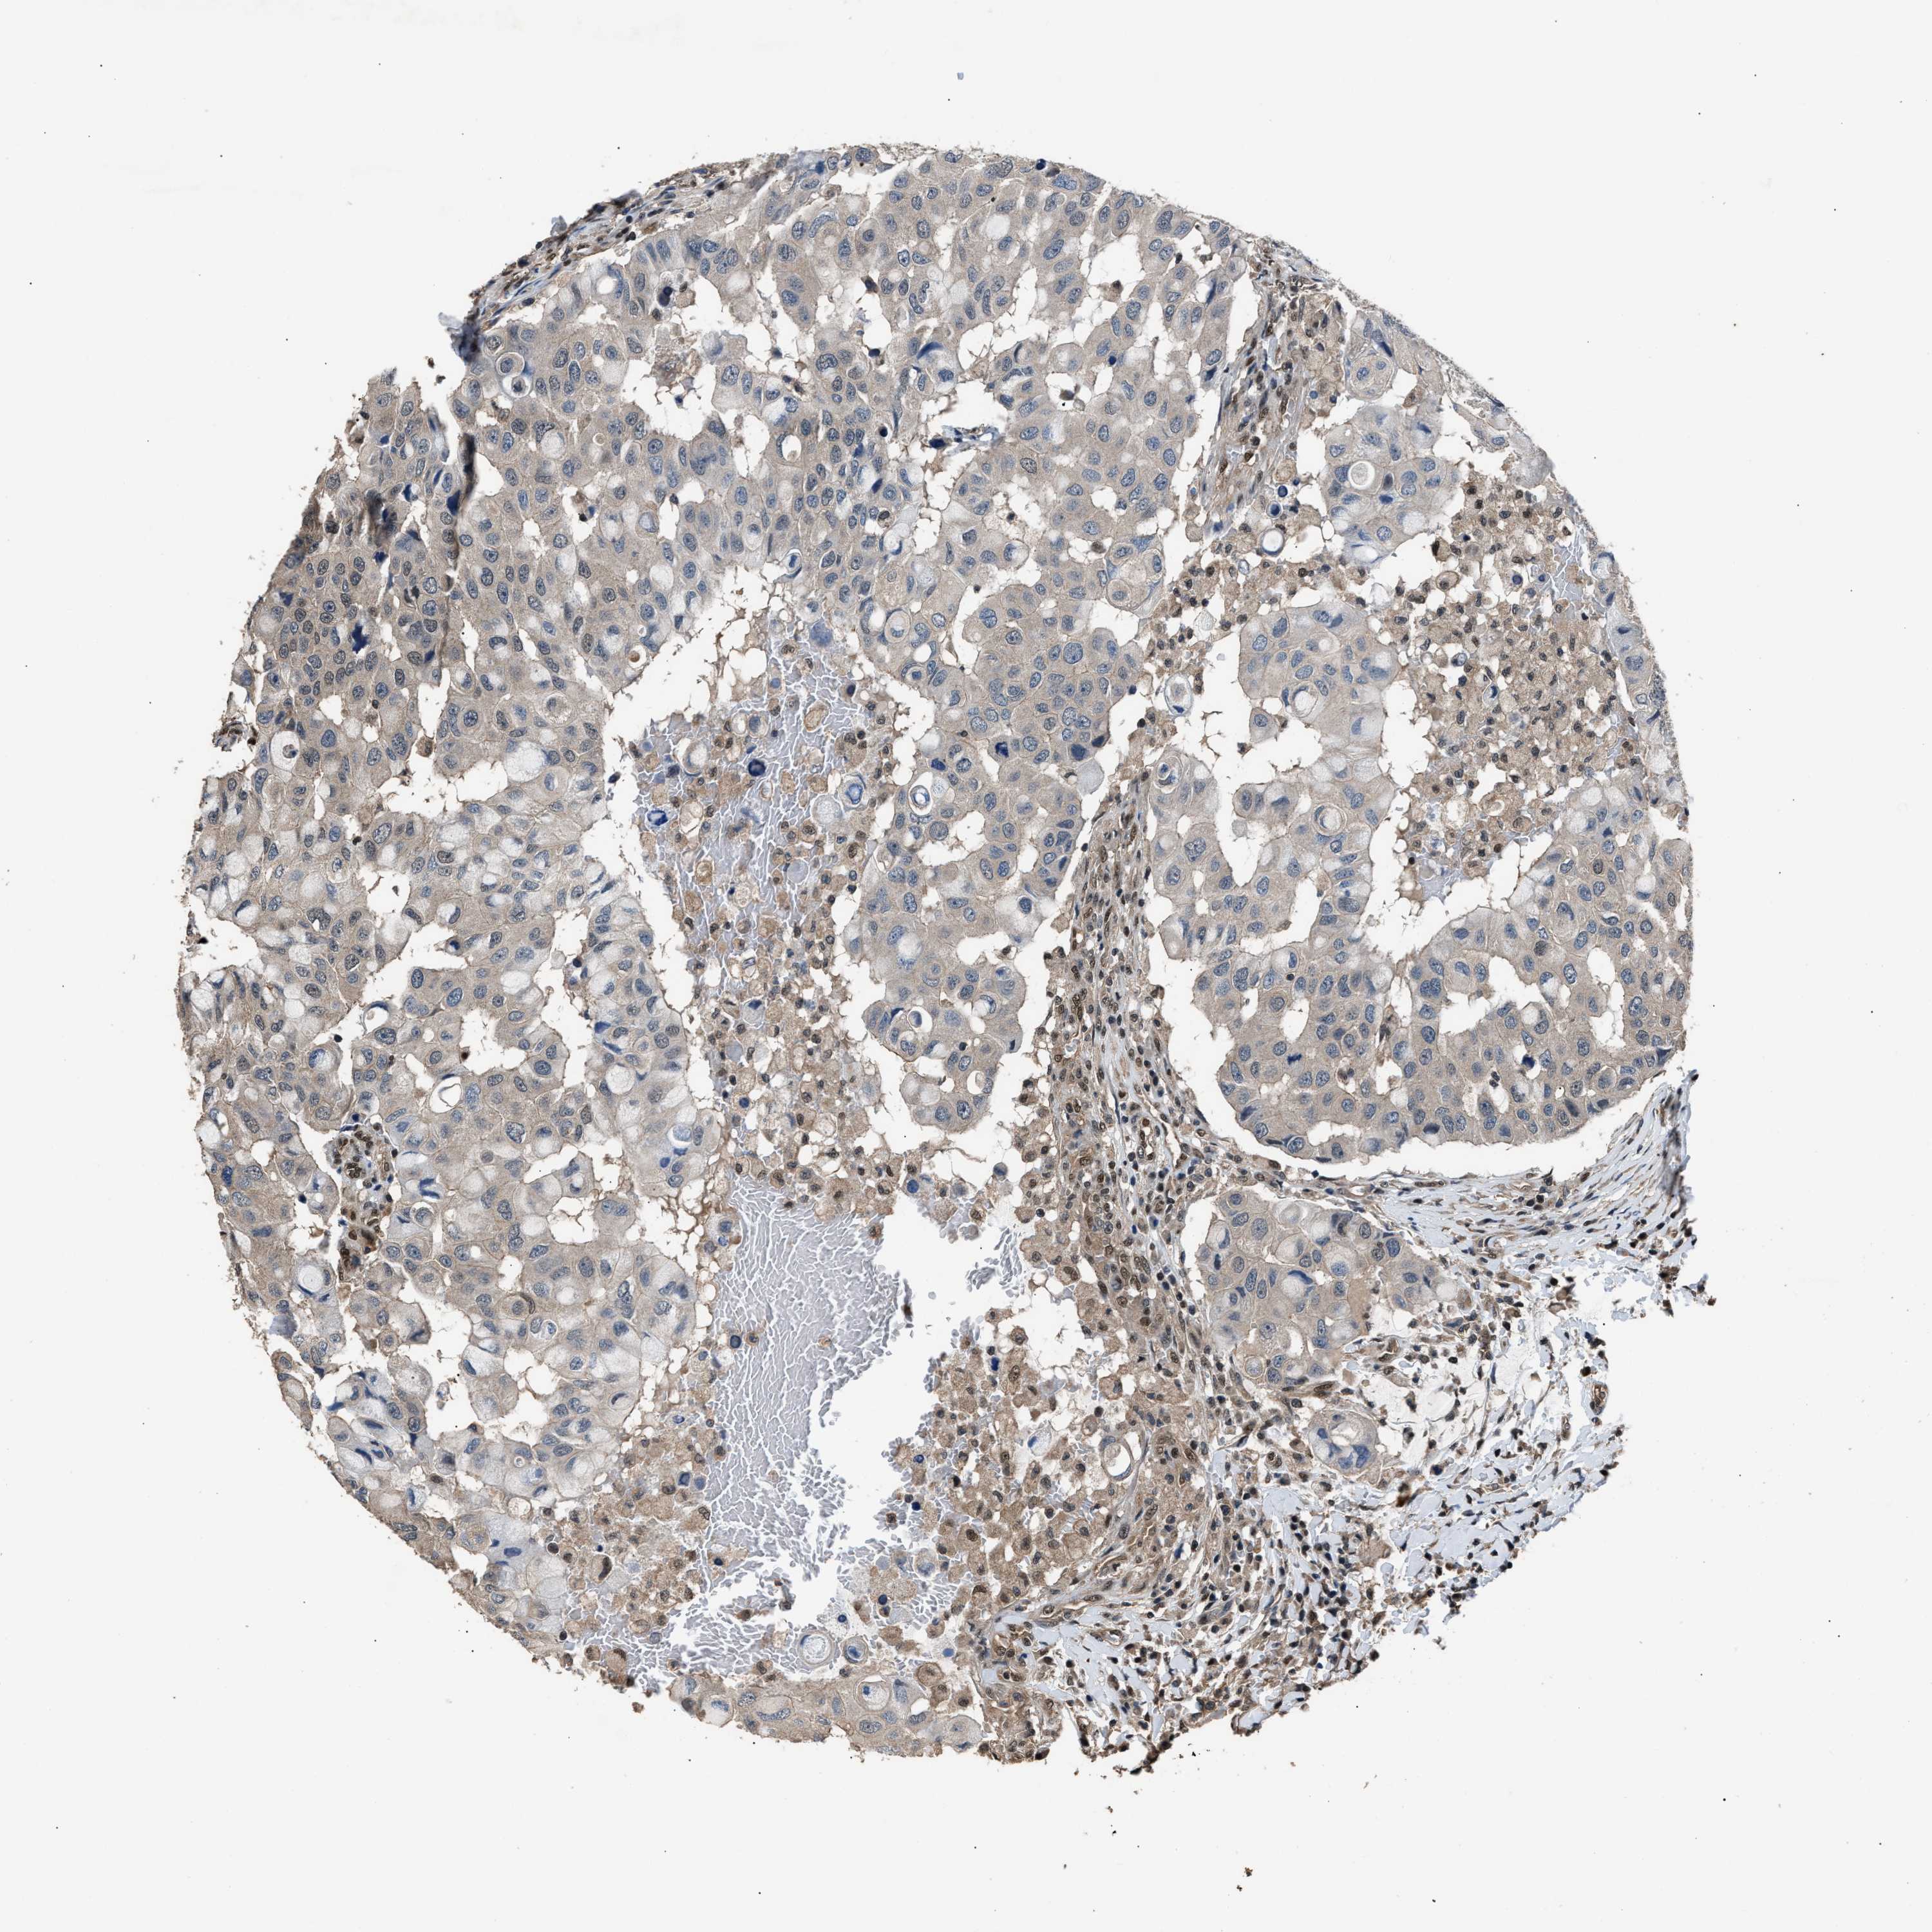

CANCER BREAST CANCER Show tissue menu

BRCA TCGA BRCA VALIDATION PROTEIN EXPRESSION